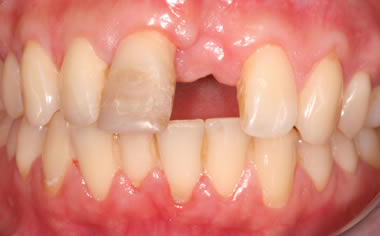

Missing upper front tooth replaced by dental implant and crown